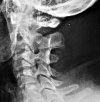

Рентгенография шейного отдела позвоночника

Рентгенография шейного отдела позвоночника. Рентгенологическое исследование нижних шейных (за исключением I-II) и верхних грудных позвонков. Показан при подозрении на переломы шейных позвонков III-VII, нарушения развития, дегенеративно-дистрофические и опухолевые процессы. Это выполняется в двух проекциях (прямой и боковой), при необходимости назначаются дополнительные (наклонные) проекции. Не требует специальной подготовки, может проводиться срочно или по плану, в стационаре или амбулаторно. Техника не показана во время беременности и в детстве. При наличии свежих травм и угрожающих жизни состояний противопоказаний нет.

Стандартное исследование проводится в двух проекциях (прямой и боковой). В то же время грудные позвонки III-VII и I-III видны на снимке в прямой проекции, а шейные позвонки I-VII видны на боковой рентгенограмме. Верхние грудные позвонки на боковом снимке не видны, так как они перекрываются тенями костей плечевого пояса. Во время рентгенографии шейного отдела позвоночника в прямой проекции пациент лежит на спине. Голова слегка наклонена назад. Боковой снимок выполняется в положении больного сидя или стоя. Чтобы не допустить совпадения теней костей плечевого пояса с изображениями нижних шейных позвонков (особенно у пациентов с короткой шеей), плечи пациента опускаются вниз. Если рентгенограмма сделана стоя, пациент получает небольшую нагрузку. Если тест проводится в сидячем положении, субъекта просят схватить кресло за кресло руками и активно опустить его плечи.

В некоторых случаях (для обследования межпозвоночных суставов и межпозвонковых отверстий) в ортопедии и травматологии рентгеновские изображения назначаются в дополнительных косых проекциях. Во время обследования пациент стоит или сидит под углом от 30 до 45 градусов лицом или спиной (в зависимости от требуемого типа дифракции рентгеновских лучей - передняя косая или задняя косая) относительно направления рентгеновских лучей.